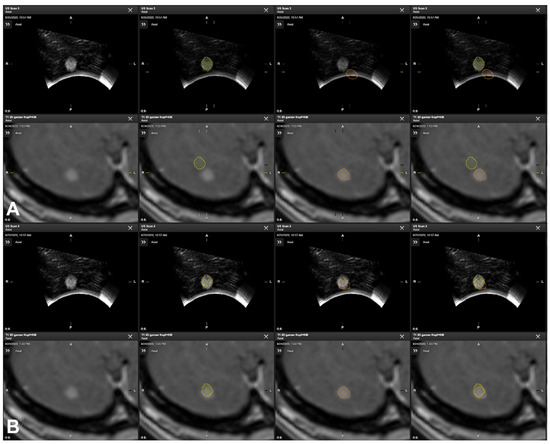

2.6. Additional Postprocessing Using Rigid Image-Based Co-Registration

- Saß, B.; Carl, B.; Pojskic, M.; Nimsky, C.; Bopp, M. Navigated 3D Ultrasound in Brain Metastasis Surgery: Analyzing the Differences in Object Appearances in Ultrasound and Magnetic Resonance Imaging. Appl. Sci. 2020, 10, 7798. [Google Scholar] [CrossRef]